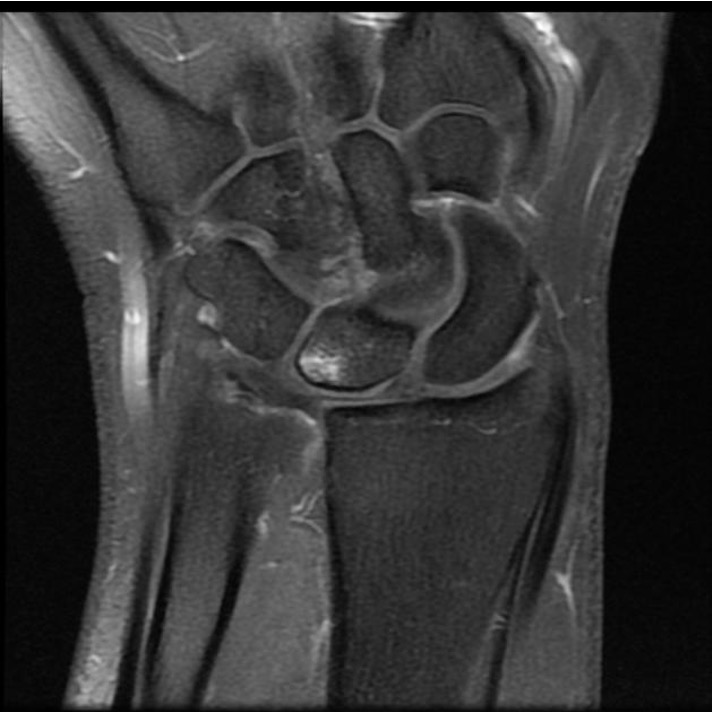

MRI

Normal

TFCC tears

Ulna sided tear

Radial sided TFCC tear

Central TFCC tear

Ulno-carpal abutment

Ulnocarpal abutment and lunate chondromalacia

Ulna positive with ulnocarpal osteoarthritis